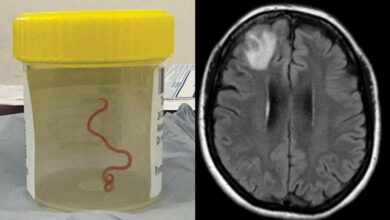

สยอง! แพทย์เจอ พยาธิตัวกลม 8 เซนติเมตร อาศัยอยู่ในสมอง เคสแรกของโลก

สุดสยอง แพทย์เจอ พยาธิตัวกลม 8 เซนติเมตร อาศัยอยู่ในสมอง หลังจากที่ผู้ป่วยมีอาการหลงลืมและซึมเศร้า ถือเป็นเคสแรกของโลก เมื่อวันที่ 28 สิงหาคม เว็บไซต์ สกายนิวส์ รายงานเรื่องราวสุดสยองในประเทศออสเตรเลี